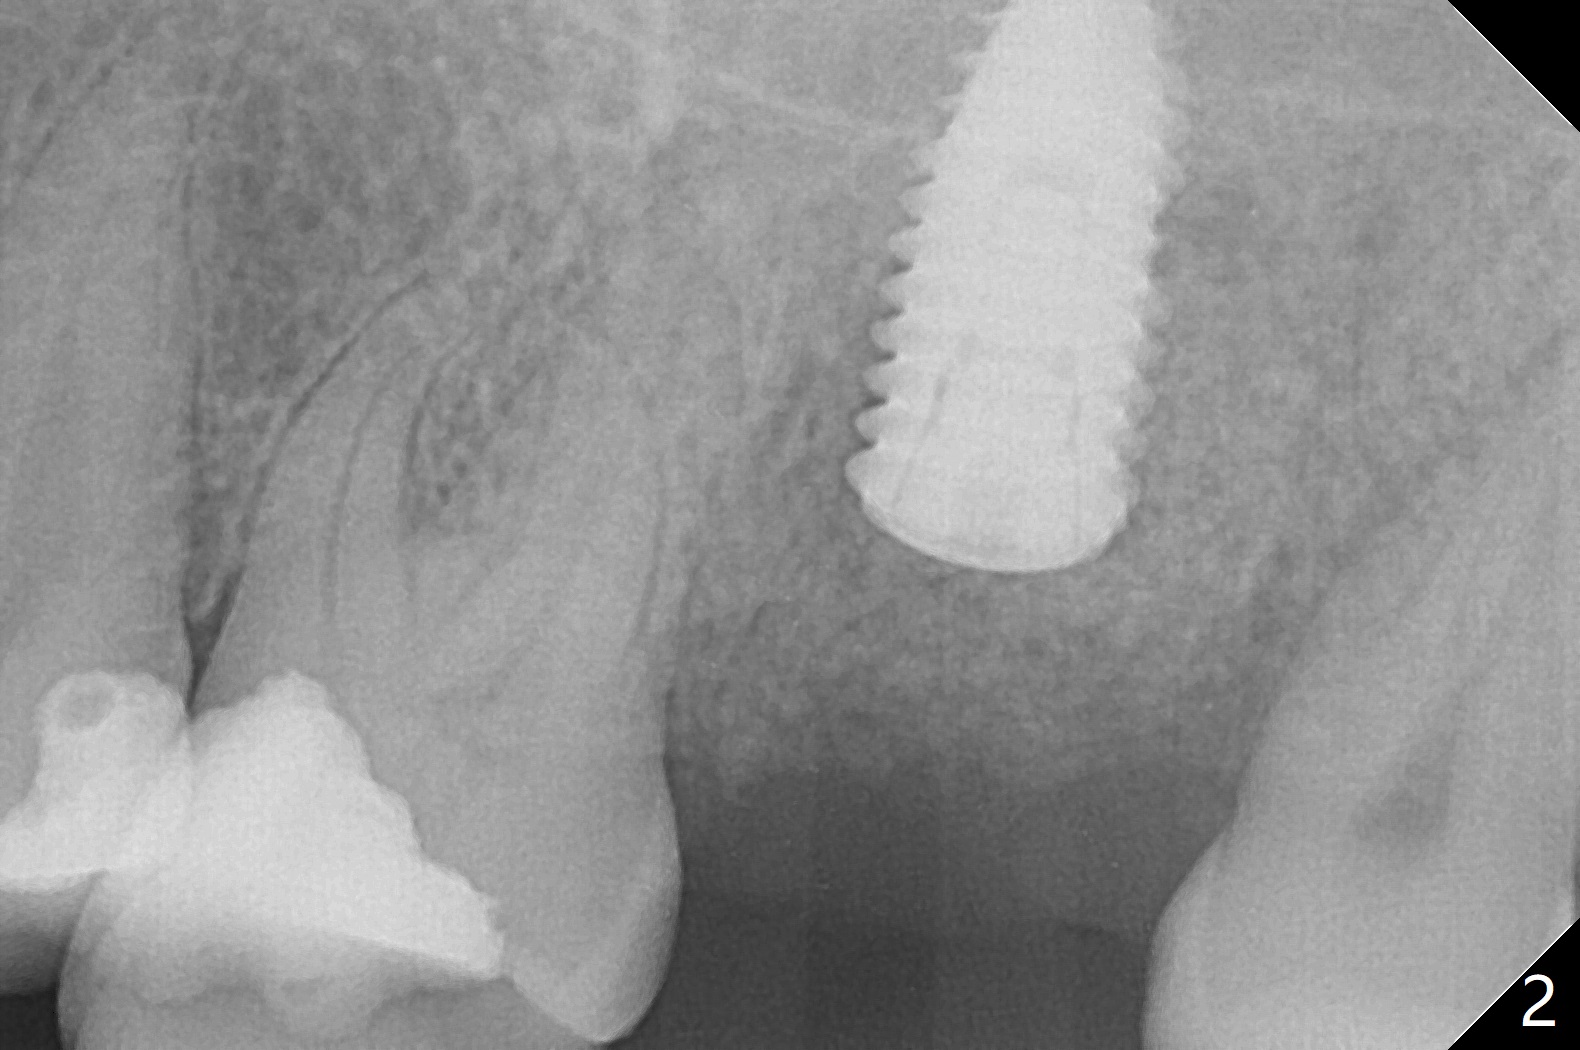

The longest (12 mm) bone trimmer seems not to work over the guide at #15.  When osteotomy finishes, the guide is removed.  The sinus floor happens to have been removed, whereas the sinus membrane remains intact.  After partial insertion of a piece of PRF membrane (due to hemorrhage) and Vanilla graft for sinus lift, a 5x10 mm implant is placed with 15 Ncm.  The implant appears to be short and placed deep (Fig.1,2).  When an implant is not too large, it can be placed ~ 1 mm subcrestal (vs. 2-3 mm for this case) in spite of the palatal wall defect.  A cover screw is used, followed by allograft (Fig.1 *).  The latter is covered with another piece of PRF membrane, collagen membrane and periodontal dressing.